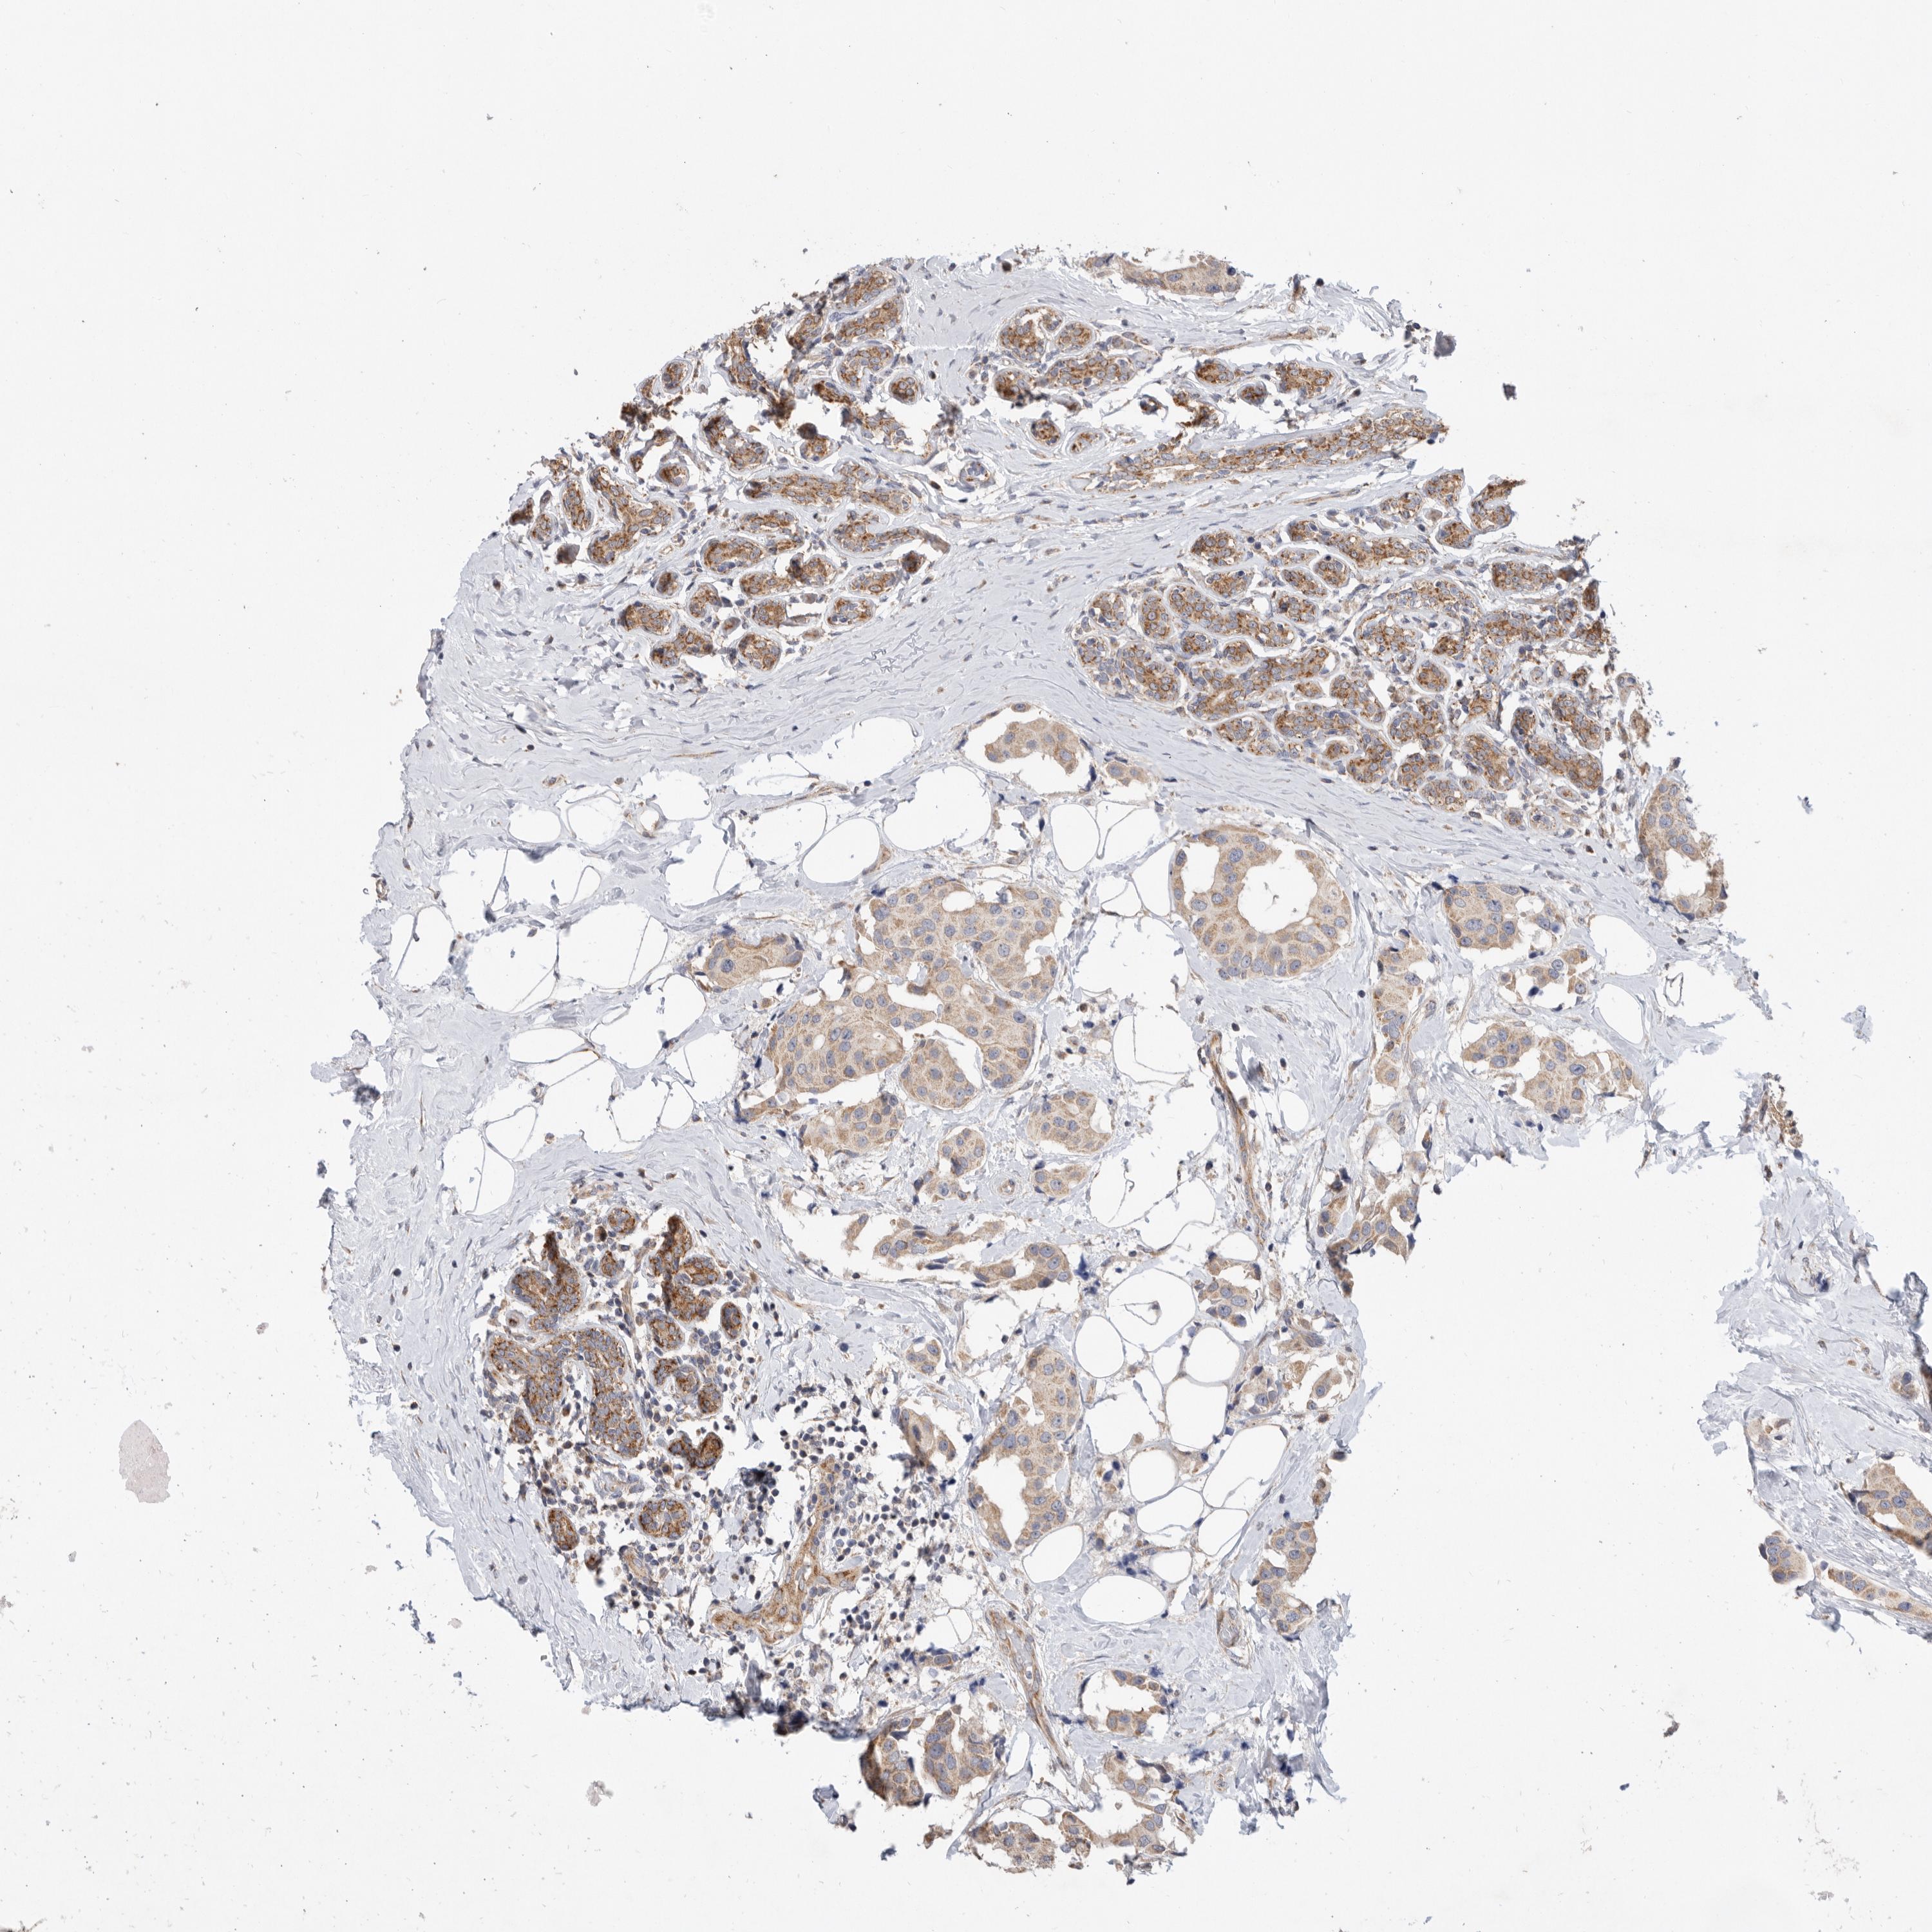

CANCER BREAST CANCER Show tissue menu

BRCA TCGA BRCA VALIDATION PROTEIN EXPRESSION